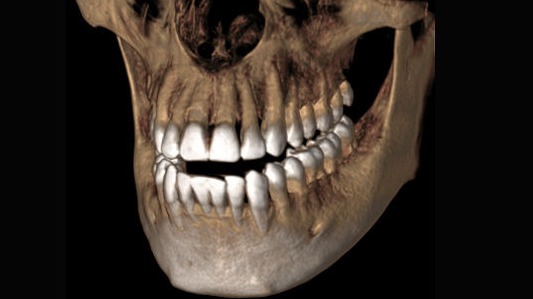

Modo de alta definición

Para determinadas indicaciones, por ejemplo, la visualización de los canales de raíces finas, el modo de alta definición (HD) muestra todos los detalles necesarios.